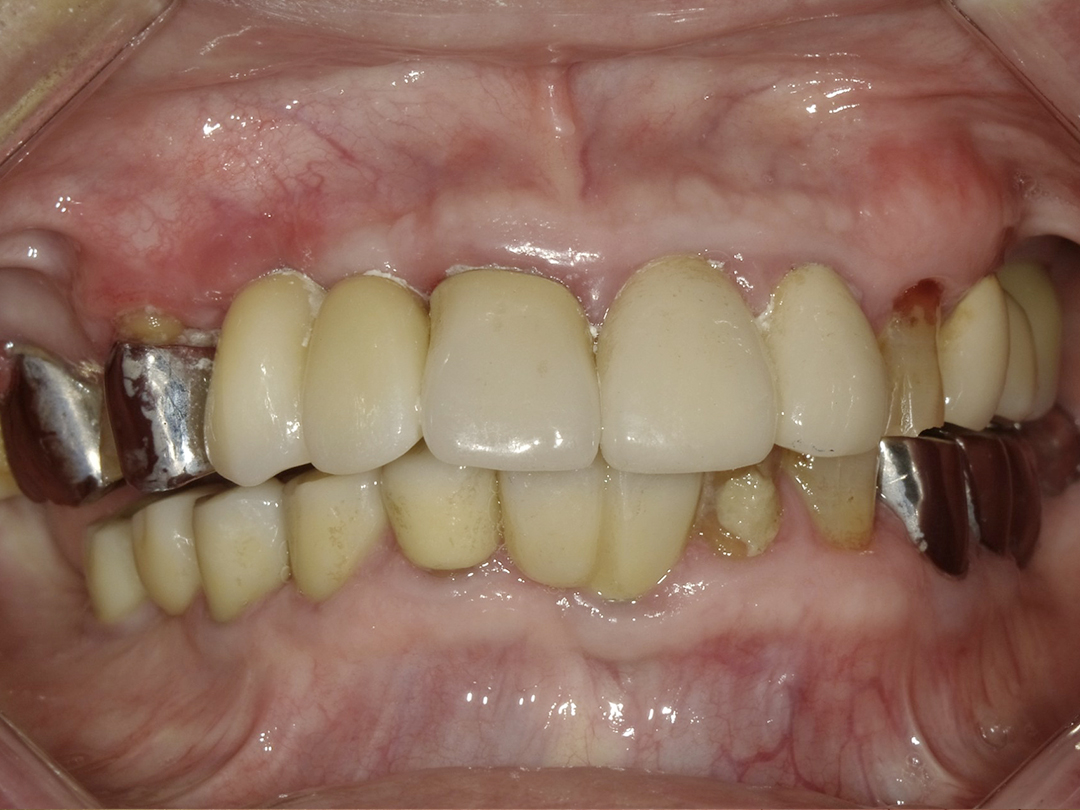

ALL ON全口重建是由4-6 顆植體(依條件而定)成,專為多顆缺牙或全口無牙患者設計的創新全口重建技術,僅需4-6 支植體即可支撐一整排固定式假牙,大幅減少手術次數與成本,並縮短療程時間。

當天手術、當天裝牙,快速恢復日常功能

固定式牙齒,告別活動假牙的不便

美觀自然,提升生活品質與自信